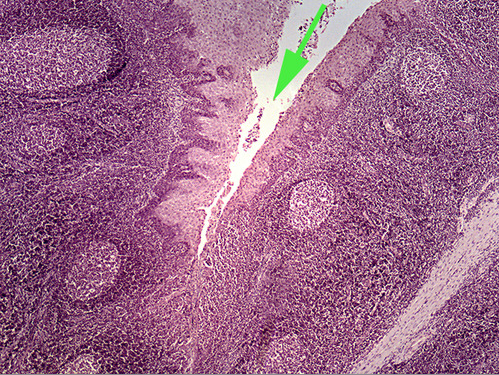

Areas of diffuse lymphatic tissue are found in the walls of the structures marked by the green arrows. They are called the///small intestine

The diffuse lymphatic tissue found in the structure marked by the green arrow is called peyer's PATCH

The green arrow is indicating the peyer's patch in this area of the small intestine. It is made up of a dense accumulation of what kind of cells?//lymphocytes

The green arrow is indicating a tonsilar crypt

diffuse lymphatic tissue called peyer's patches in the wall of the intestinal tract.